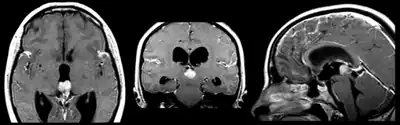

Pineoblastoma localized predominantly in posterior part of the third ventricle